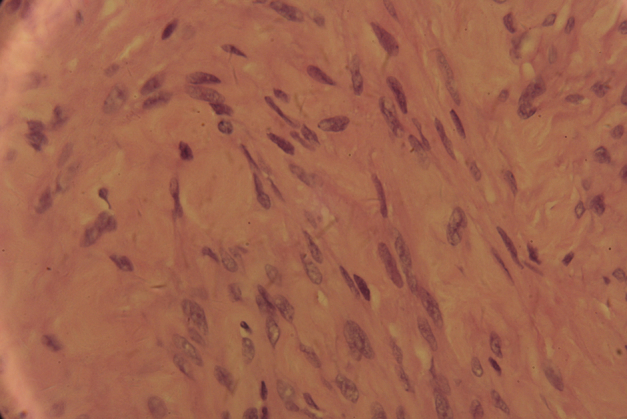

The patient was discharged on postoperative day 4. Histology of the paraffin specimen confirmed the diagnosis of a benign leiomyoma (Figure 3, Figure 4).

Figure 4.

Histopathological appearance confirming leiomyoma (HE ×400).